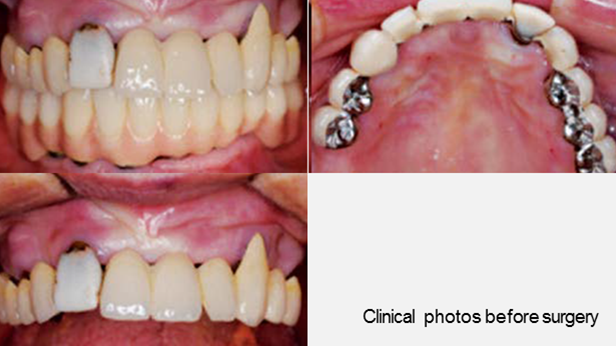

Clinical case: A Full transition from natural teeth to all-on-6 bridges

with AnyRidge implants

- Courtesy of Dr. Rabih Abi Nader, UAE -

Keywords

Full-mouth rehabilitation, minimal layering, Zirconia, all-on-6, life changing result, edentulous ,Dr. Rabih Abi Nader, AnyRidge

Products:

AnyRidge implant system